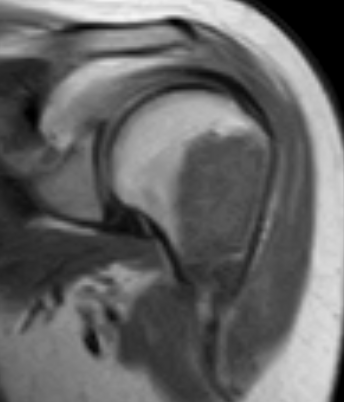

MRI

Large, central enchondroma